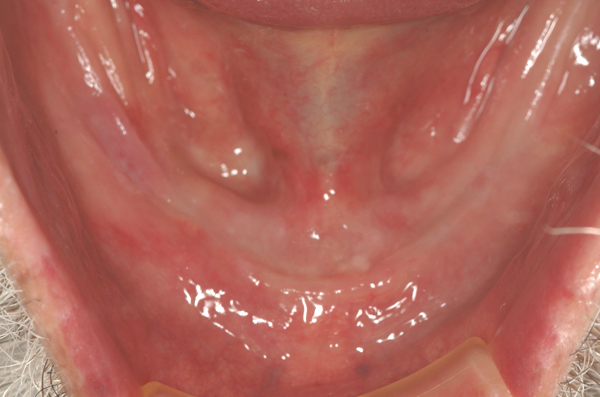

ロケーター

下顎がすべて欠損の為、2本インプラントを埋入し、入れ歯に組み込むロケーターにて咬む機能が改善。

手術 22万円×2本 上部構造 10万円×2本(税別)

- 喫煙者の方は、インプラント周囲炎やインプラント脱離のリスクが高まります。

- 当院ではナイトガードを使用していただいています。

- 骨幅が足りない、神経までの距離が短いケースは手術を行えないこともあります。